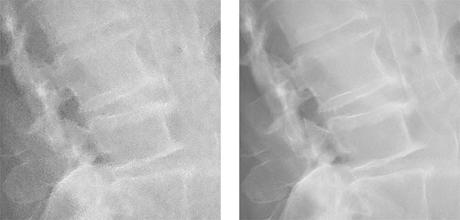

Application de la NR intelligente

gauche : image conceptuelle utilisant le NR conventionnel de Canon

à droite : image conceptuelle après application de la réduction du bruit intelligente